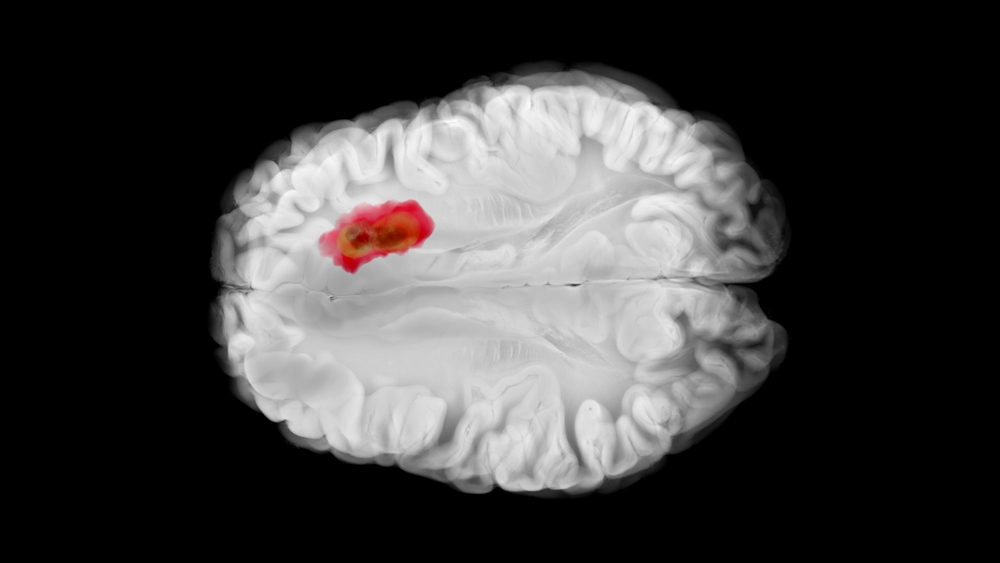

Антисекреторные препараты, ингибиторы протонной помпы (ИПП), часто назначаются пациентам с глиобластомой для профилактики стероид-ассоциированого гастрита и пептической язвенной болезни.

Целью систематического обзора и мета-анализа было оценить исходы глиобластомы на фоне применения ИПП и антацидов, активирующих ALDH1A1.

Согласно результатам мета-анализа у пациентов с впервые диагностированной глиобластомой терапия ингибитором протонной помпы ассоциировано со снижением выживаемости.